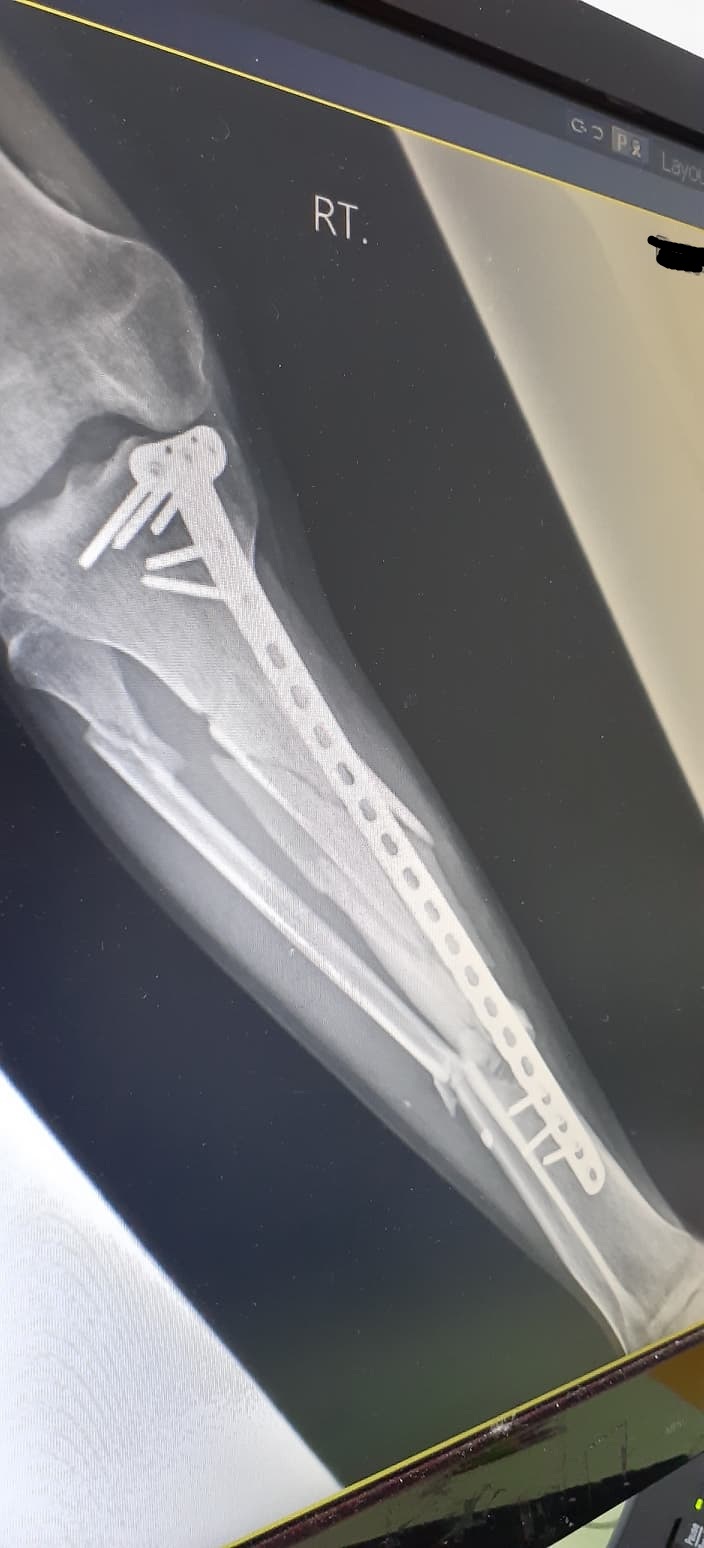

จากภาพเอกซเรย์ที่ปรากฏ หลังจากผ่าตัดมาแล้ว10เดือนครับ คุณหมอให้ลงน้ำหนักได้บ้างโดยการใช้ไม้ค้ำยันเป็นตัวช่วยพยุง แต่แกบอกว่าถ้ามีอาการเสียวให้หยุดเดิน1-2อาทิตย์ตรงนี้หมายความว่าผมสามารถเดินแบบลงน้ำหนักได้ตลอดใช่ไหมครับ (อาการเวลาเดินค่อนข้างจะเจ็บช่วงน่องขามาก)

ภาพข้างล่างหลังจากผ่าตัด4เดือน